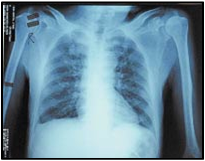

Severe acute respiratory syndrome (SARS) is a respiratory disease in humans which is caused by the SARS corona virus. There has been one near pandemic to date, between November 2002 and July 2003, with 8,096 known infected cases and 774 deaths worldwide being listed in the World Health Organization's (WHO) 21 April 2004 concluding report. Within a matter of weeks in early 2003, SARS spread from the Guangdong province of China to rapidly infect individuals in some 37 countries around the world. Mortality by age group as of 8 May 2003 is below 1 percent for people aged 24 or younger, 6 percent for those 25 to 44, 15 percent in those 45 to 64 and more than 50 percent for those over 65. For comparison, the case fatality rate for influenza is usually around 0.6 percent but can rise as high as 33 percent in locally severe epidemics of new strains. The mortality rate of the primary viral pneumonia form is about 70 percent.